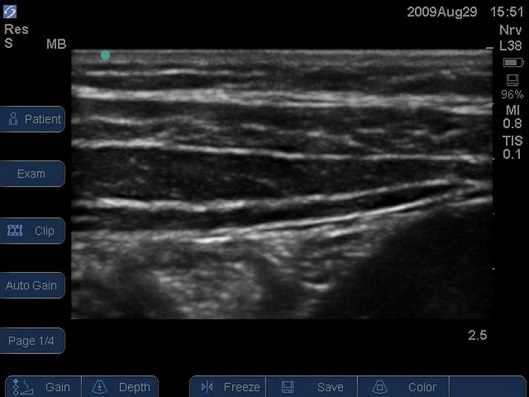

- Identify the peritoneum and then the lateral abdominal muscles from deep to superficial (transversus abdominis, internal oblique, and external oblique).

- The target is the fascial plane between the transversus abdominis and the internal oblique muscles.

e) Inguinal Herniorrhaphy - Label the image below

A anterior

B posterior

C Transversus Abdominis muscle

D Internal Oblique muscle

E External Oblique muscle

F Peritoneum